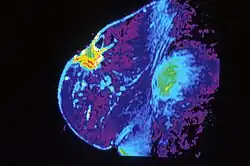

Breast MRI, an alternative to mammography, has shown substantial progress in the detection of breast cancer. The available literature suggests that the sensitivity of contrast-enhanced breast MRI in detection of cancer is considerably higher than that of either radiographic mammography or ultrasound and is generally reported to be in excess of 94%.[32] The specificity (the confidence that a lesion is cancerous and not a false positive) is only fair ('modest'),[33] (or 37%–97%[32]), thus a positive finding by MRI should not be interpreted as a definitive diagnosis. The reports of 4,271 breast MRIs from eight large-scale clinical trials were reviewed in 2006.[34]

Currently, American and European guidelines both recommend MRI screening as the optimum imaging modality but differences exist in regards to screening for certain patient subgroups. MRI has shown specific utility in women with extremely dense breast tissue. By using supplemental MRI in these women who had otherwise normal mammography results, there was a diagnosis of significantly fewer interval cancers than when using mammography alone during a two-year period.[35]

One of the other advantages of MRI screening is in cancer treatment. Specifically, MRI shows increased detection of small cancers which have less associated lymph node involvement and consequently decreased frequency of interval cancers which affect survival and mortality.[36] Additionally, MRI Is also shown to be more accurate than mammography, ultrasound, or clinical exam in evaluating treatment response to neoadjuvant therapy.[37]